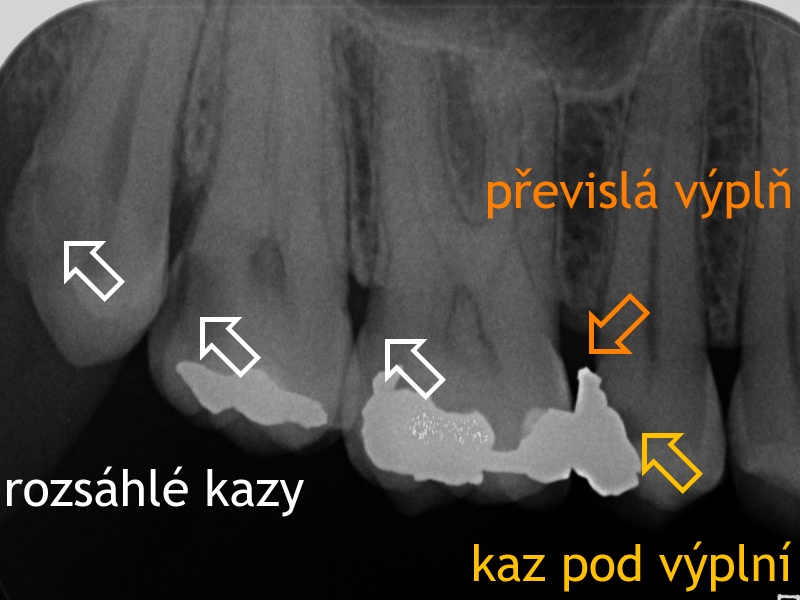

Rentgenový snímek se zřetelnými kazy a převislou amalgámovou výplní. Kazy se na rentgenových snímcích zobrazují jako tmavší skvrny, amalgámové výplně mají kontrastní bílou barvu.